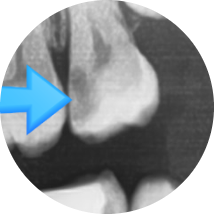

위 엑스레이 사진은 처음 방문하였을 때 엑스레이 사진입니다.

충치가 매우 심해 신경치료 해야 한다고 설명하였으나

환자분은 치아사진을 보면 치아가 썩은 것처럼 보이지 않는다면서(화살표 부분)

방치하다가 6개월이 지난 후 치아가 깨져서 오게 되었습니다.

이미 엑스레이 사진에서 충치가 매우 심함을 알 수 있고

치아 겉부분은 아주 얇게 남아있고 안은 무른 충치로 가득 차있음을 예상할 수 있습니다.